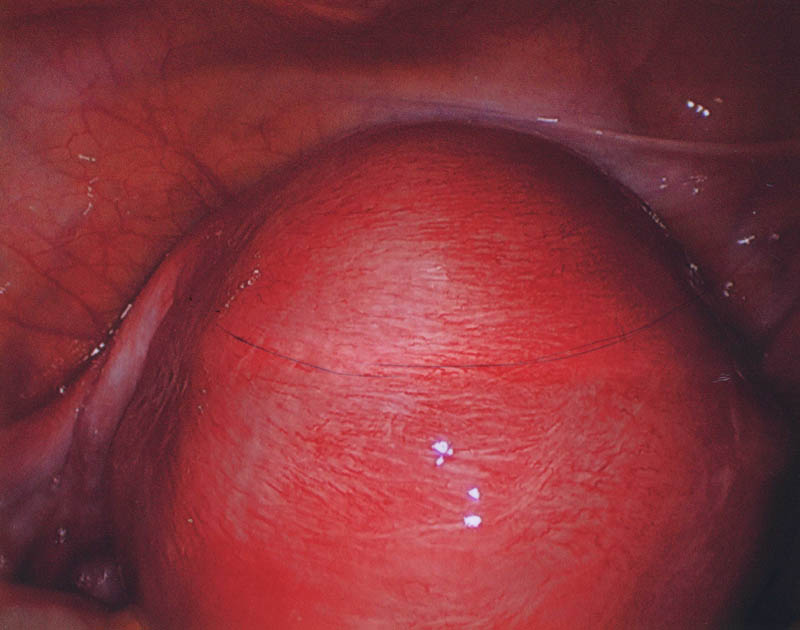

- лапароскопия: позволяет с высокой точностью визуализировать внутреннюю часть матки и проводить забор патологического материала для проведения гистологического исследования и выбора тактики лечения;

Уровень развития современной медицины позволяет проводить операции по удалению очагов эндометриоза и рассечению спаек максимально безопасным способом, с применением органосохраняющих лапароскопических вмешательств. Активно используются лазерные методики оперативного лечения.

Малоинвазивная резекция патологических тканей позволяет сохранить в полной мере репродуктивные функции женщины и подарить ей надежду на возможное материнство в дальнейшем.